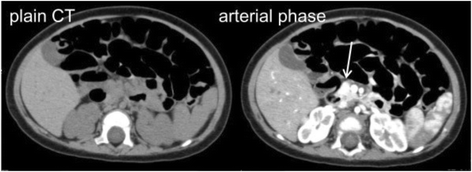

Fig. 2From: Focal form of congenital hyperinsulinism clearly detectable by contrast-enhanced computed tomography imagingCT scan. A hyperenhancing nodule was identified on the arterial phaseBack to article page